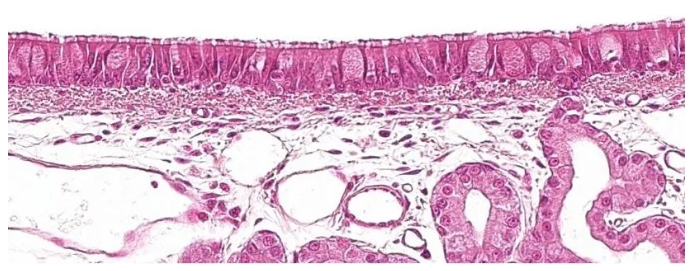

呼吸系統(tǒng)的第一部分,傳導(dǎo)區(qū)或呼吸區(qū),從鼻腔到細(xì)支氣管的最后一個(gè)分支,還包括與鼻腔相連的鼻竇和副鼻竇、鼻咽部和喉部。 所有這些管狀結(jié)構(gòu)都內(nèi)襯有帶有杯狀細(xì)胞的纖毛假?gòu)?fù)層上皮(圖1),這是呼吸粘膜的主要防御系統(tǒng)之一,粘液纖毛系統(tǒng)。 該系統(tǒng)由呼吸道上皮細(xì)胞的纖毛,以及來(lái)自杯狀細(xì)胞的分泌物和位于呼吸道粘膜下方的漿液腺組成。它們的主要功能是清除通過(guò)吸入空氣進(jìn)入的顆粒。腺體在纖毛之間分泌一種透明、低粘度、富含蛋白質(zhì)的液體,形成一種促進(jìn)纖毛向上運(yùn)動(dòng)的介質(zhì)。 杯狀細(xì)胞分泌的粘液沉積在纖毛上,允許吸入的顆粒粘附。纖毛的向上運(yùn)動(dòng)將粘液推向上呼吸道;然后,粘液可以被吞下并進(jìn)入消化道,在那里被消化,或通過(guò)口腔和/或鼻腔排出。導(dǎo)致纖毛丟失的肺炎支原體,或?qū)е律掀ぜ?xì)胞破壞的豬流感或呼吸道冠狀病毒等病原體,通過(guò)破壞這種防御系統(tǒng)來(lái)發(fā)揮致病作用。 與呼吸道粘膜相關(guān)的是支氣管相關(guān)淋巴組織(BALT),其中淋巴細(xì)胞與來(lái)自外部病原體的抗原相互作用,引起特定的防御反應(yīng),從而避免了全身免疫反應(yīng)。其特征是通過(guò)IgA的體液免疫反應(yīng)的介導(dǎo),IgA通過(guò)主動(dòng)運(yùn)輸?shù)姆绞竭x擇性地分泌在粘膜表面。

圖1:帶有杯狀細(xì)胞的纖毛假?gòu)?fù)層上皮,是呼吸系統(tǒng)的特征